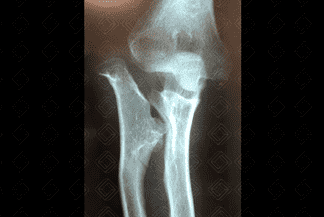

Texto alternativo para a imagem Figura 1. Créditos: Dra Elazir Mota - Rio de Janeiro/RJ

Descrição das figuras 1 e 2: Radiografia do antebraço e cotovelo em AP evidenciando múltiplas exostoses ósseas (figura 1 - setas vermelhas) na metáfise proximal do rádio e distal da ulna. As exostoses ósseas originam-se no ápice das metáfises em sentido contrário às epífises.